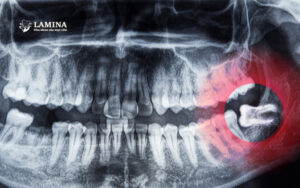

Nếu bạn thấy vùng răng khôn sưng đau, chảy máu, hoặc có mùi hôi, hãy đến nha khoa chụp phim X-quang. Chỉ hình ảnh mới cho biết răng đó còn mọc hay đã hoàn tất.

4.1. Khám và chụp X-quang xác định tình trạng răng

Bước đầu tiên và quan trọng nhất. Bác sĩ sẽ kiểm tra hướng mọc, độ lệch, và xác định có cần can thiệp hay chỉ cần vệ sinh, giảm đau.